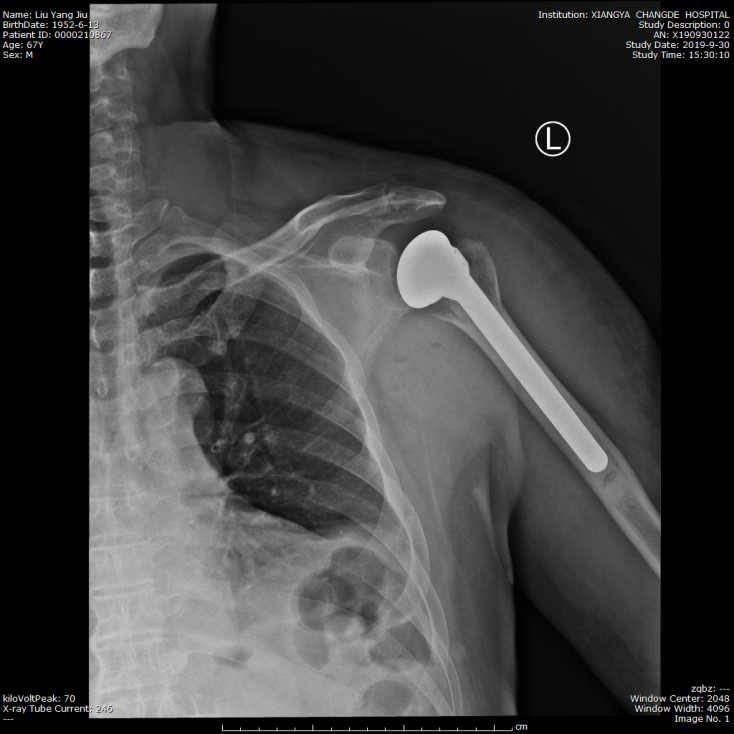

术后复查肩关节正位片

骨科主任张朝跃教授带领的关节外科团队对患者进行详细的病史询问,全面的体格检查及详尽分析临床影像学资料,明确诊断为左肩关节脱位并肱骨近端骨折(Neer四部分骨折),有骨质疏松症,鉴于患者创伤严重,骨折为粉碎型伴有骨质疏松,骨折复位困难,钢板内固定术后肱骨头坏死几率大。张朝跃教授决定行左侧人工肱骨头置换手术,术前与患者及其家属充分沟通,分析手术的必要性、适应症以及肩关节置换手术治疗安全、恢复快,可以改善肩关节功能等特点,刘爷爷及其家属充分理解并决定行该手术治疗。